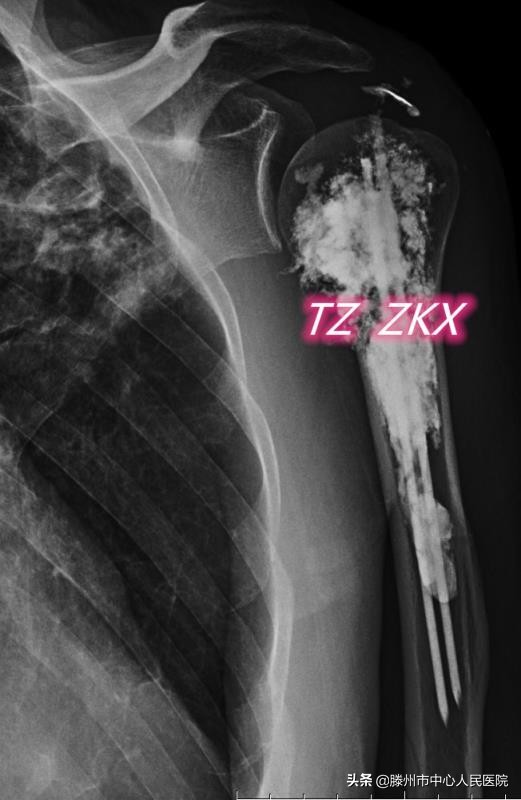

8月11日,张开贤主任医师团队在麻醉科的协助下,采用臂丛麻醉,在CT引导下经皮穿刺,首先对病变区域进行微波消融,利用高温使肿瘤发生凝固性坏死,然后在肱骨髓腔内置入两根克氏针,最后注射骨水泥,使克氏针、骨水泥与肱骨融合在一起,从而起到杀灭肿瘤、缓解疼痛、增加骨骼的稳定性、预防病理性骨折的作用。

微波消融联合钢筋混凝土技术治疗骨转移为国内领先的微创治疗技术,优势在于:在臂丛麻醉下进行,减少了全身麻醉对身体的不良影响;经皮穿刺完成整个治疗流程,创伤小,术后恢复快,住院时间短;在CT引导下进行,能精准地观察克氏针的空间位置、骨水泥的分布及渗漏情况,保证了治疗的安全性,同时与DSA下操作相比,减少了射线对医务人员的辐射。